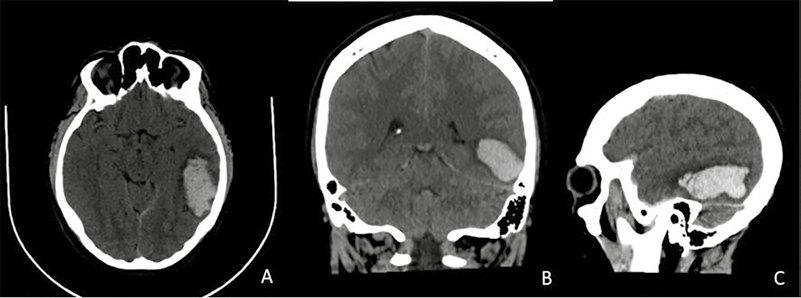

Posteriormente, se realiza tomografía de cráneo simple y se aprecia morfología de cráneo

sin alteraciones, con presencia

de área hiperdensa rodeada de edema pelilesional, localizada en región subcortical que se extiende a la sustancia blanca del lóbulo temporal izquierdo. La lesión mide 5,4 x 2,7 x 2,8 cm con un volumen de 21,3 cc.

En relación con hemorragia intraparenquimatosa, presenta compromiso

en espacio subdural de fosa temporal del mismo lado produciendo un desvió mínimo de estructuras

de la línea media hacia

la derecha en 3 mm. También

se evidencia borramiento de surcos y cisuras en el hemisferio cerebral izquierdo relacionado con el edema

y obliteración parcial

del asta occipital del ventrículo lateral

de lado izquierdo (ver Figura 1).

Figura 1. Tomografía

computarizada de cráneo simple: A) plano axial; B) plano coronal; C) plano sagital